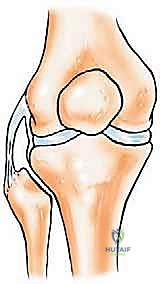

- استقرار مفصل الركبة (Knee Stability): في الجزء العلوي (رأس الشظية القريبة)، ترتبط الشظية بقوة بالرباط الجانبي الوحشي للركبة (LCL) ووتر العضلة ذات الرأسين الفخذية. هذه الهياكل ضرورية للغاية لمنع الركبة من الانحناء للخارج (Varus stress) والحفاظ على استقرار مفصل الركبة الجانبي أثناء المشي والجري.

- إذا كان الاستئصال في أعلى الشظية (رأس الشظية): يجب إعادة ربط الرباط الجانبي (LCL) ووتر العضلة ذات الرأسين بعظم الساق (الظنبوب) للحفاظ على استقرار الركبة.